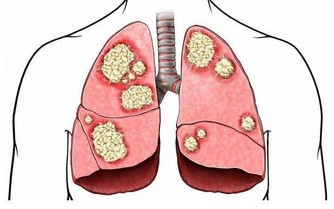

4、抗癌、延年益壽

芝麻是富硒食物,因此它還有良好的抗癌作用;